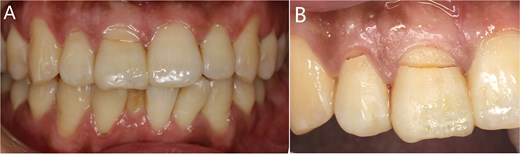

Imaging examinations

Preoperative dental film revealed 11 and 12 crown-root fracture (Fig. 2A), while results from cone beam computed tomography (CBCT) showed that the lingual fracture line of 11 tooth was located under the alveolar bone, the buccal bone was thin (<1 mm), and the height of alveolar bone was sufficient (Fig. 2B). The lingual side of 12 tooth crown was located at the top of the alveolar crest, with a root length of about 10 mm. No obvious periapical shadow was found (Fig. 2C).

Imaging examinations. (A) The dental film; (B) 11 tooth position in CBCT images; (C) 12 tooth position in CBCT images.